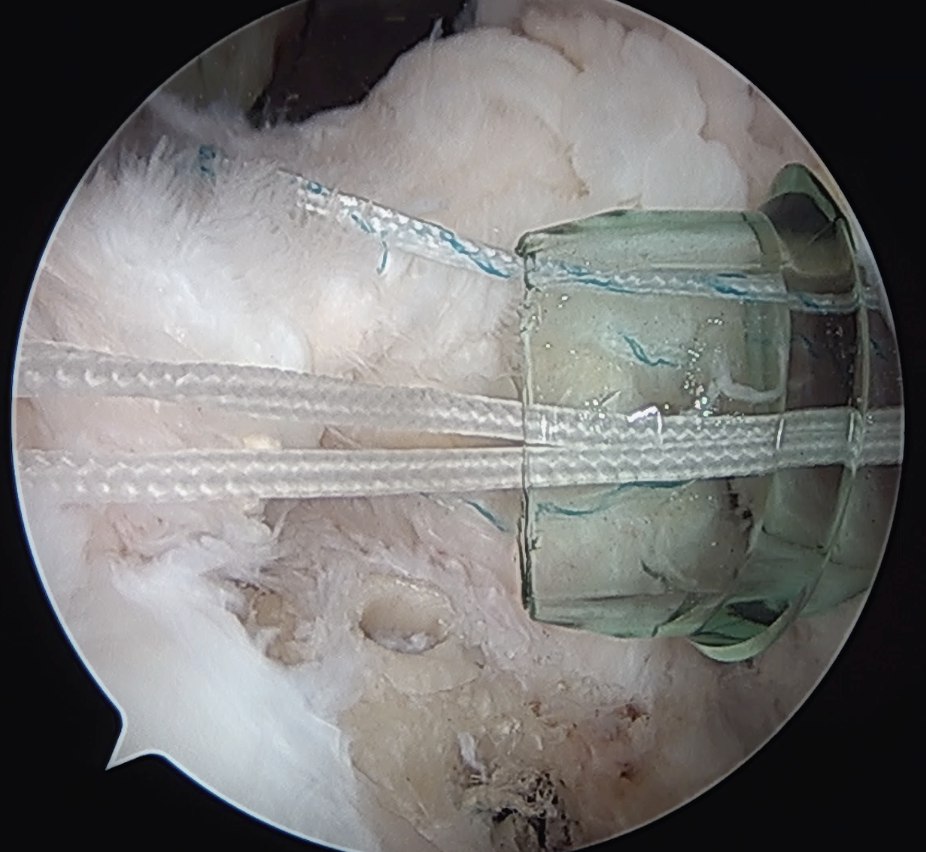

Trans-osseous equivalent / suture bridge

- cross sutures from medial row to lateral row

- increase contact between cuff and footprint

Arthroscopic Suture Bridge Cuff Repair

Double row / suture bridge

- use medial row sutures

- secure in knotless lateral row anchors

repairrepairrepair

Arthroscopic Cuff Suture Bridge RepairArthrscopic Cuff Repair